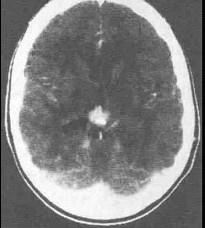

问题 关于生殖细胞瘤(如图所示)以下描述中不正确的是()

选项 A.青少年多见,恶性程度高 B.发生于松果体区者女性多,鞍上者男性多 C.鞍上为多发部位 D.对放疗、化疗敏感 E.常通过脑脊液播散

答案 B